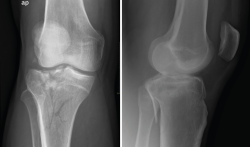

Radiología

El diagnóstico radiológico consiste en la realización de una radiografía sobre una zona del organismo para el estudio de los órganos que se encuentran en su interior.

La radiología es útil para el diagnóstico de las fracturas, luxaciones, osteoartritis o para cuantificar las desviaciones axiales y planificar las cirugías de realineación(1).

Es el procedimiento de imagen empleado generalmente como primera elección y es muy útil para la visualización de los elementos óseos, con la limitación que supone la superposición en un mismo plano de todas las estructuras atravesadas por los rayos X.

Deben hacerse proyecciones anteroposterior (AP) y lateral, generalmente con flexión de 30°, y axial de la rótula cuando se sospeche patología de esta; y proyecciones especiales oblicuas o laterales, proyecciones forzadas de varo o valgo, y AP en 45°, para valorar mejor la interlínea articular(2).

1. Lesiones traumáticas

1.1. Fracturas

1.1.1. Fémur (Figura 1)

Figura 1. Radiografías anteroposterior y lateral de rodilla: fractura longitudinal del fémur extendida a la articulación.